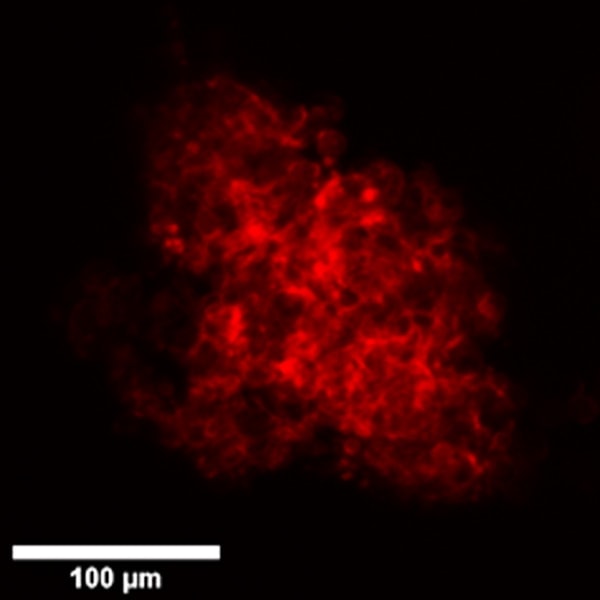

Here are shown organoids cultured in Matrigel on optical multi-well plates and generated from primary stem cells from colon cancer biopsies and stained for cytoskeleton by Phalloidin-568.

Comparison between Widefield, Confocal Spinning Disk and Super Resolution acquisitions.

X-Light V2 Confocal Spinning Disk